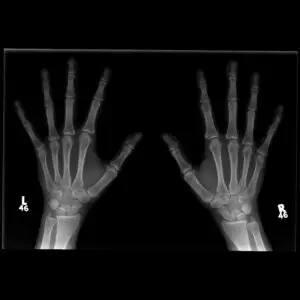

Normal hand Xray

Description & Notes